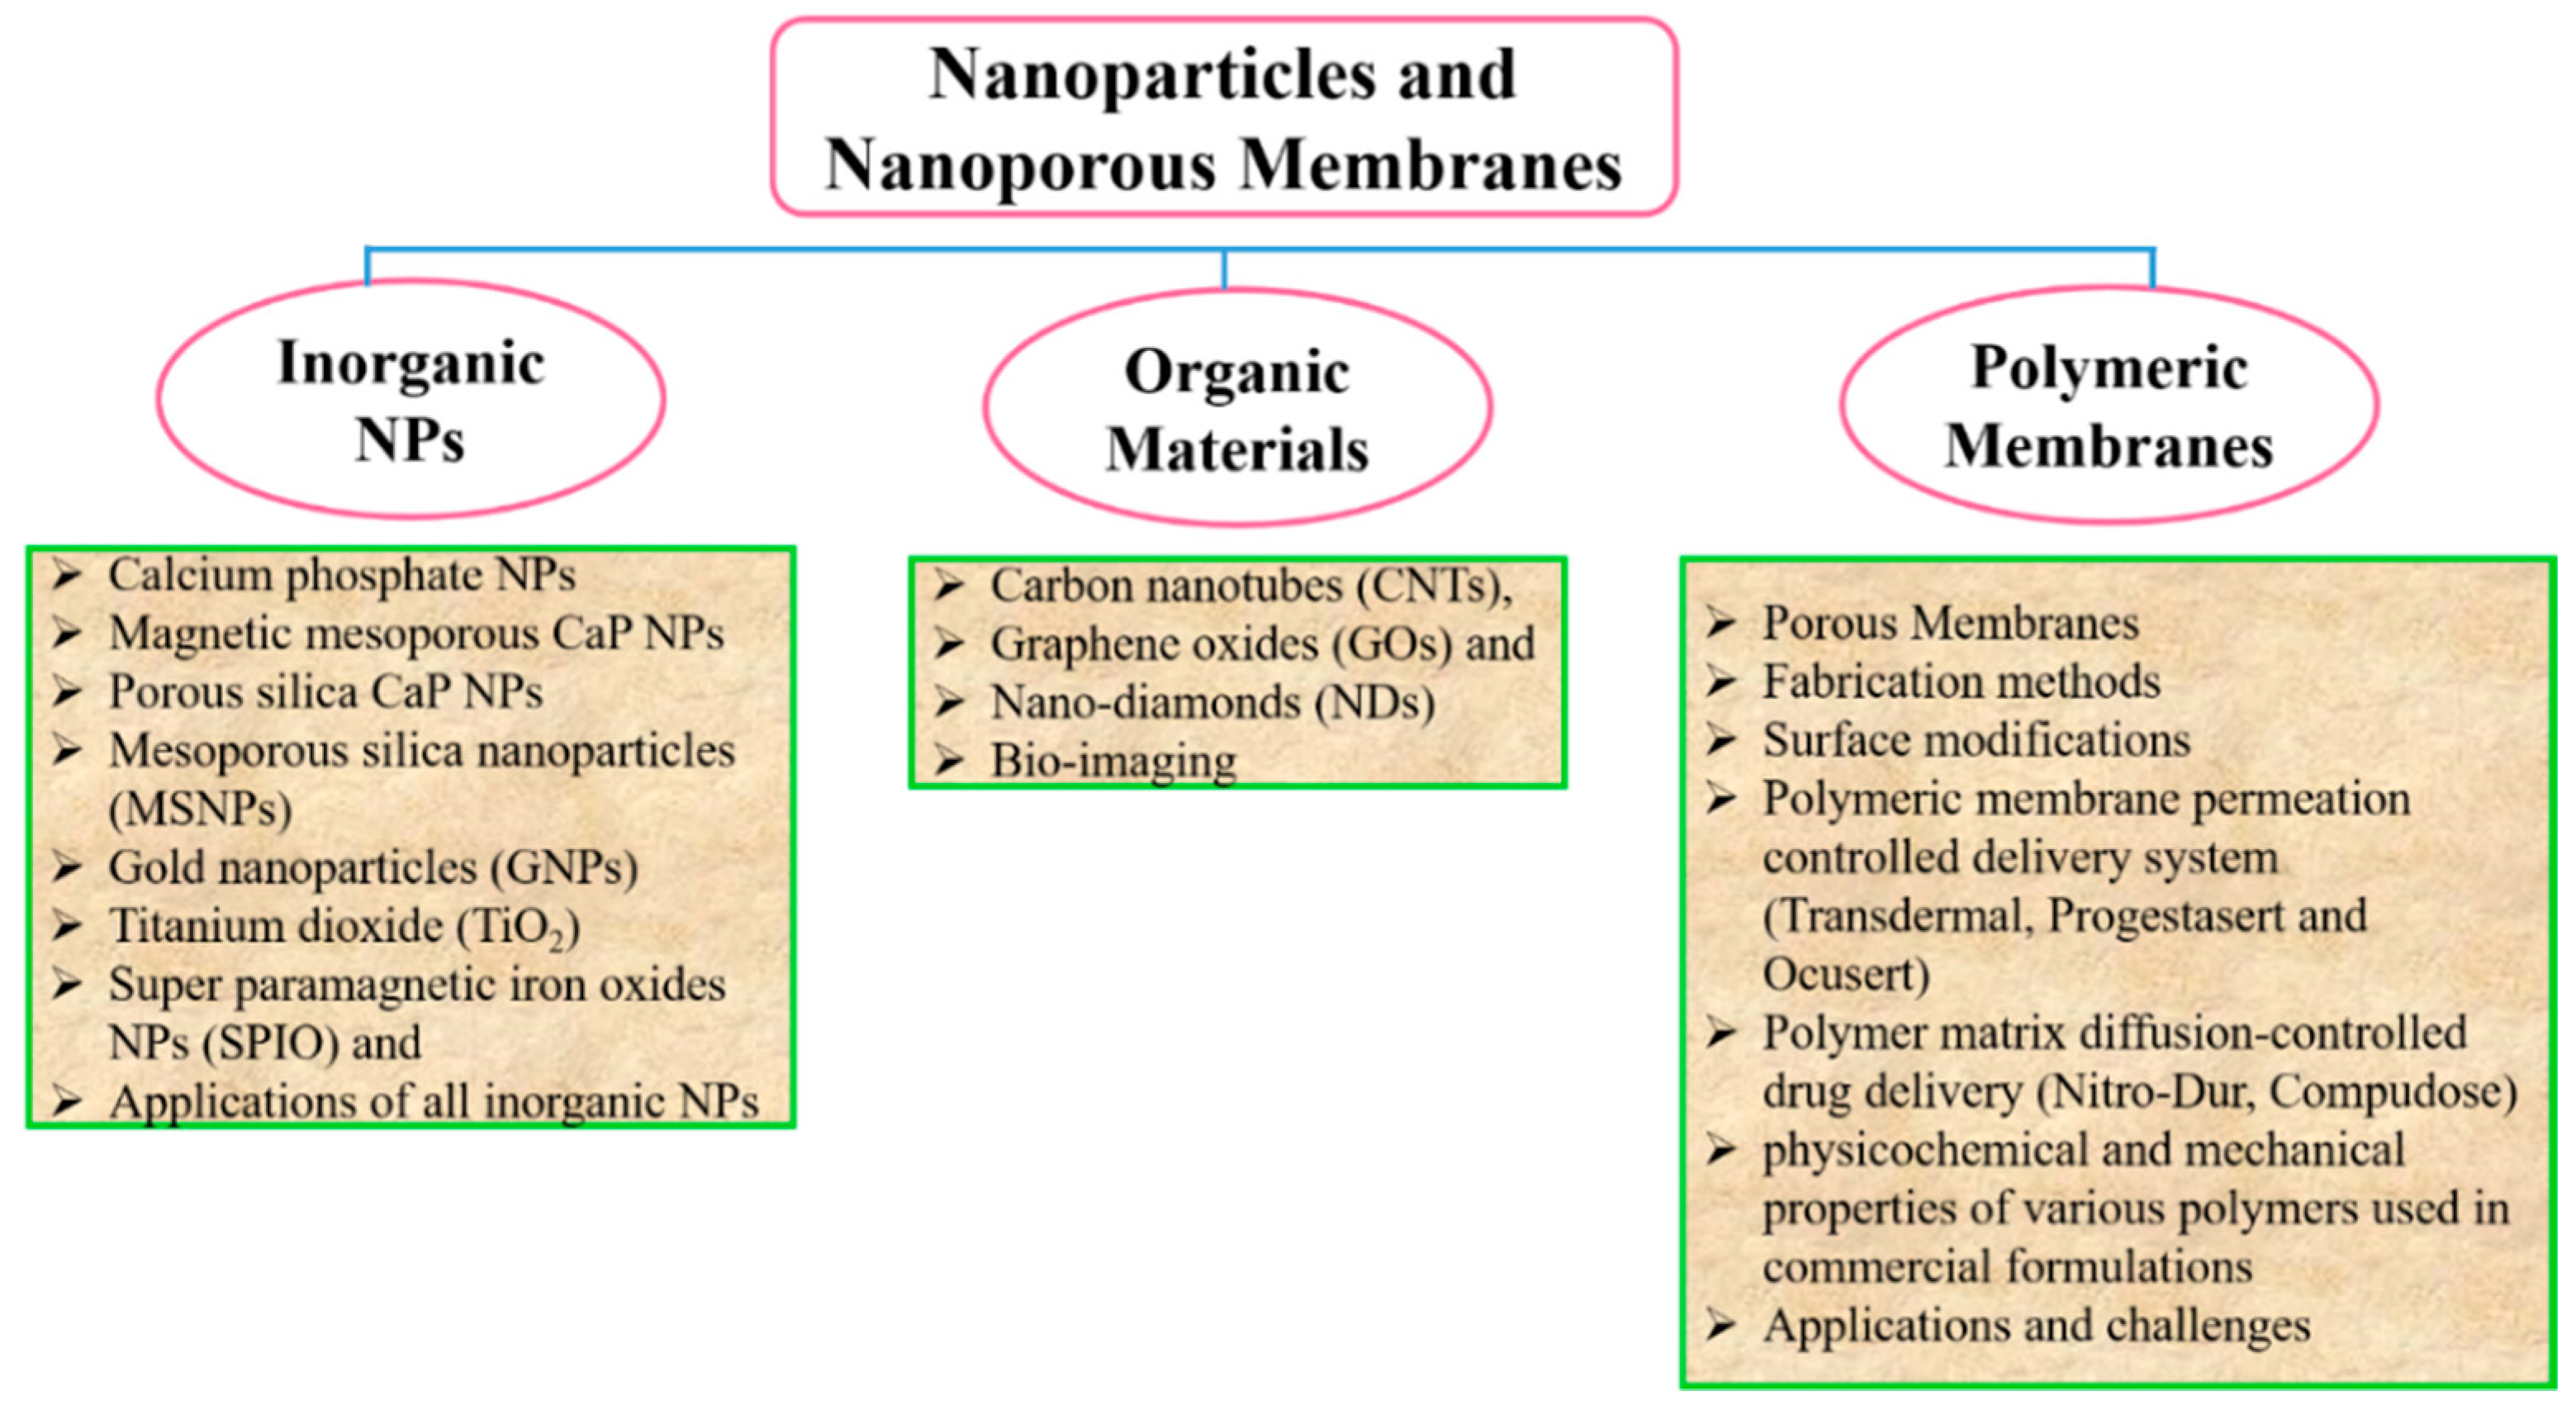

:1. Introduction

1.1. Why Nanoparticles?

1.2. Why a Nanoporous Membrane?

2. Drug Delivery System

2.1. Calcium Phosphate NPs

2.2. Carbon-Based Nanomaterials

2.3. Mesoporous Silica Nanoparticles (MSNPs)

2.4. Gold Nanoparticles (GNPs)

2.5. Other NPs Used as Drug Delivery Carriers

3. Inorganic NPs for Hard Tissue Regeneration

4. Bio-Imaging

5. Porous Membranes

5.2.1. Polymeric Membranes